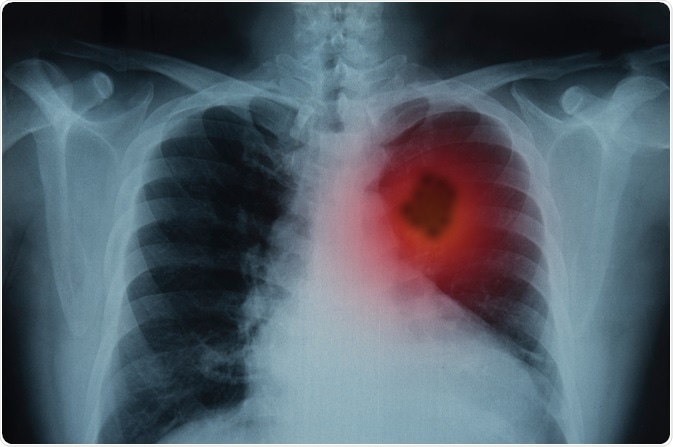

Image Credit: Create Jobs 51/Shutterstock.com